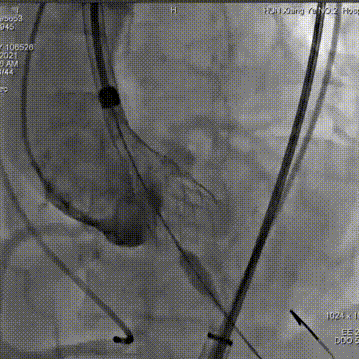

手术采用22 mm TaurusAtlas球囊进行预扩,植入AV23TaurusNXT主动脉瓣。第一次释放后位置偏高,瓣膜完全回收。第二次释放到工作位,检测左右冠血流灌注情况,考虑左瓣叶的瓣尖钙化影响左冠脉血流,使用第二次回收后,预置LCA保护。之后再次释放瓣膜至工作位,在GuidezillaII支撑保护下送 4.0×18mm 支架至 LAD 近段,之后瓣膜精准释放,后用22mm TaurusAtlas球囊后扩。术后即刻经胸超声心动图评估显示少量瓣周漏,平均跨瓣压差为10mmHg,主动脉瓣口峰值流速为2.3m/s,有效瓣口面积为1.80cm²,血流动力学指标理想。

术中影像

主动脉根部造影可见重度钙化

22mm球囊预扩

瓣膜第一次释放

未达到最佳位置,完全回收

重心定位后,第二次释放到瓣膜工作位,发现LCA灌注缝隙狭小

预置LCA保护

完全回收,第三次定位释放,瓣膜位置良好

瓣膜工作位释放“烟囱支架”

瓣膜完全释放后22mm球囊后扩

释放后造影